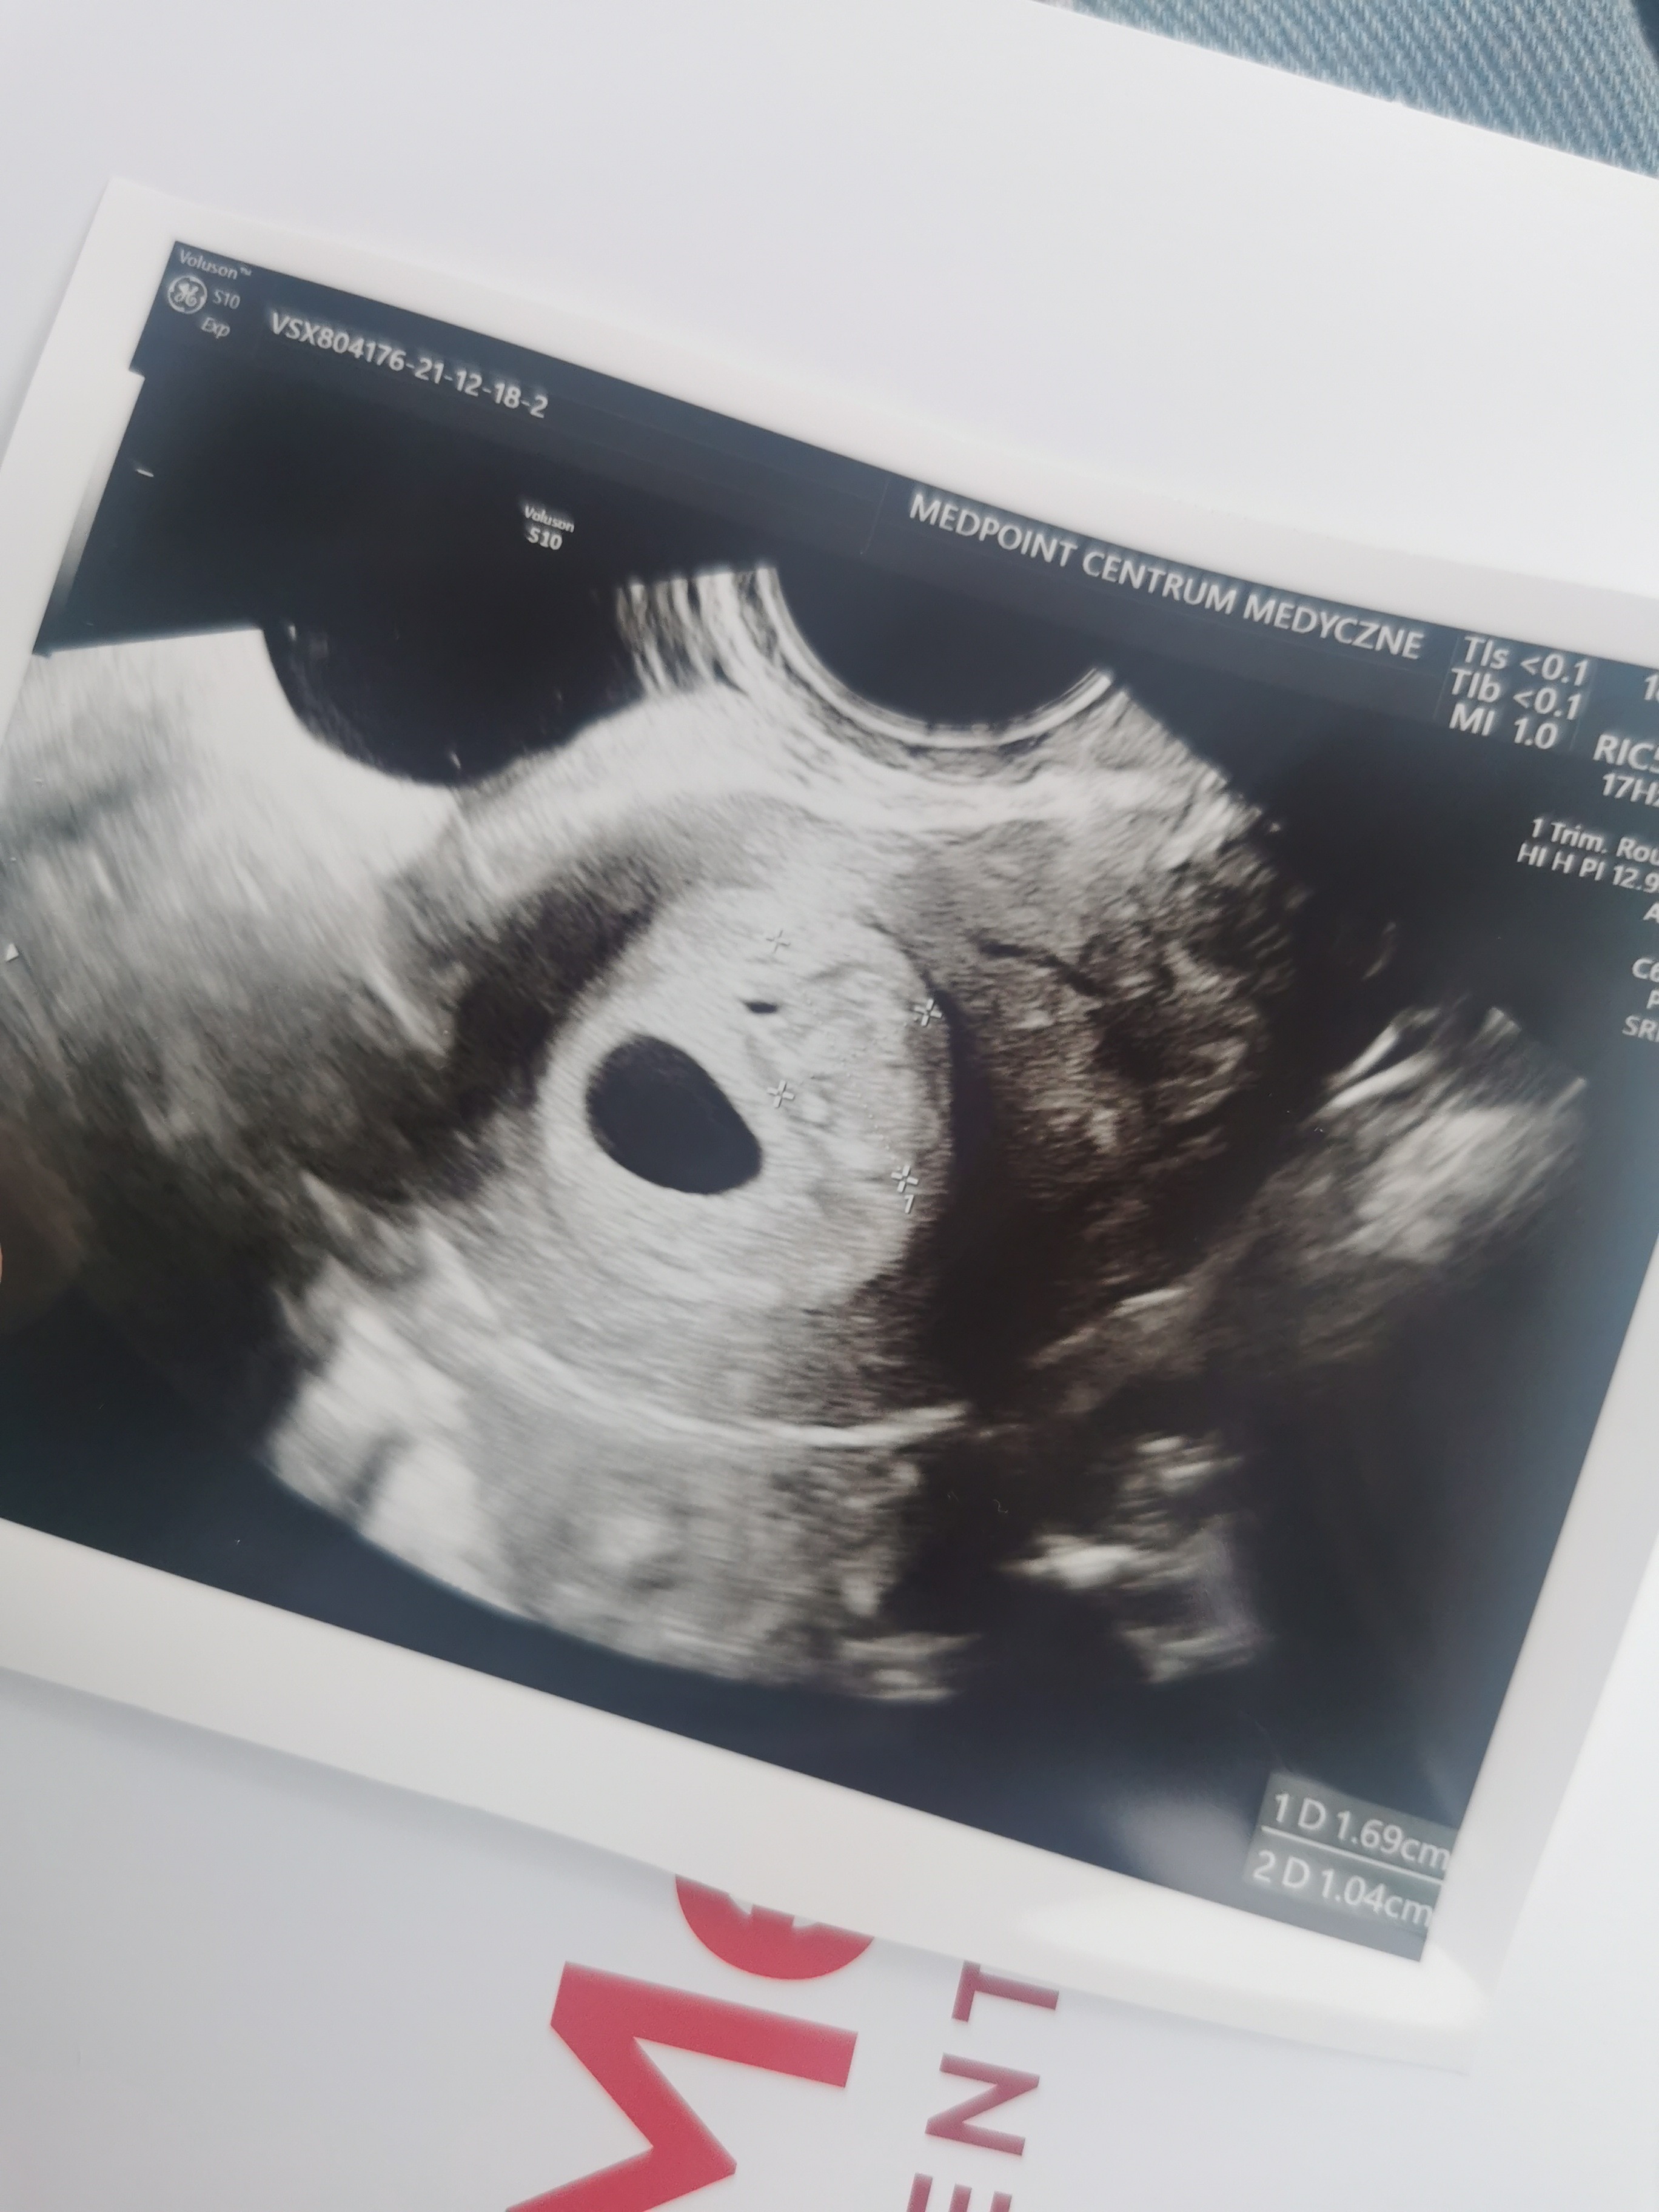

Hej dziewczyny.bylam wczoraj na usg. Mam wyliczone dokladnie 6 tyg wczoraj i mamy pecherzyk 1.1,cialko zolte i zarodek 3.3 z zaczynajacymi sie tlic komorkami i to bylo wlasnie tworzace sie serduszko . Dziękuję za Wasze wsparcie♥️ jedyny problem to maly krwiak 1.7x1, ale nie przylega do pęcherzyka i jest dość jasny na obrazir wiec prawdopodobnie sie wchlania. Odpoczywam i czekam na Dzidzie♥️

Załączniki

• IMG_20211218_133342.jpg

IMG_20211218_133342.jpg

957,7 KB · Wyświetleń: 117

• IMG_20211218_133252.jpg

IMG_20211218_133252.jpg

945,1 KB · Wyświetleń: 116